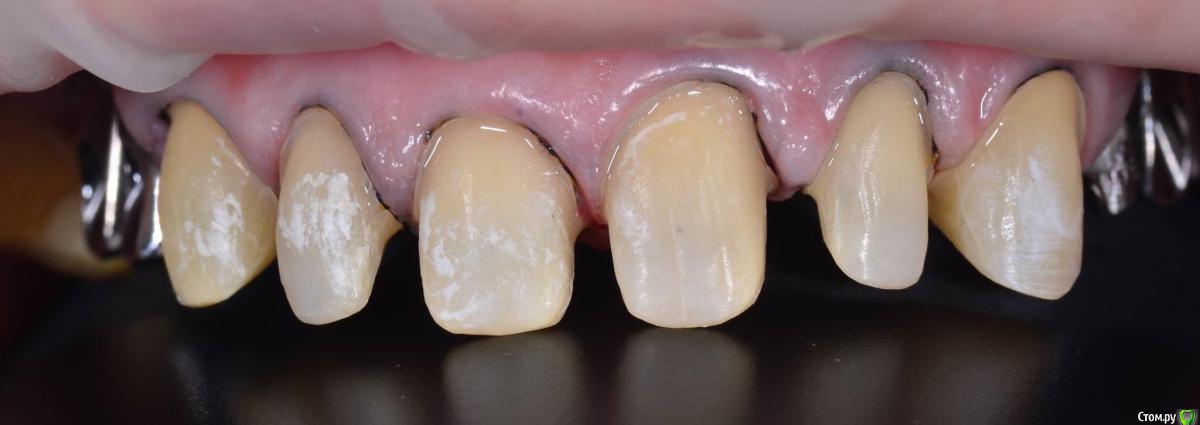

AndyAndy Опубликовано 5 апреля, 2016 Поделиться Опубликовано 5 апреля, 2016 Такое ощущение, судя по фото, что абатменты полированные. Техник не проводит пескоструйную обработку супрагингивальной части абатмента? Ссылка на комментарий

Карен Аванесов Опубликовано 5 апреля, 2016 Поделиться Опубликовано 5 апреля, 2016 Пескоструйка ухудшит гигиену. Ссылка на комментарий

togrul Опубликовано 5 апреля, 2016 Автор Поделиться Опубликовано 5 апреля, 2016 Такое ощущение, судя по фото, что абатменты полированные. Техник не проводит пескоструйную обработку супрагингивальной части абатмента?Да абатменты такие пришли с фрезерного центра. Проблем небыло с фиксацией. Ссылка на комментарий

AndyAndy Опубликовано 5 апреля, 2016 Поделиться Опубликовано 5 апреля, 2016 Да абатменты такие пришли с фрезерного центра. Проблем небыло с фиксацией.Проблемы могут появиться, если фиксировать на цемент типа Cem-implant, improve - банальная расцементировка. В моей практике 2 раза так бывало, пропустили пескоструйную обработку Ссылка на комментарий

AndyAndy Опубликовано 5 апреля, 2016 Поделиться Опубликовано 5 апреля, 2016 Пескоструйка ухудшит гигиену.Карен, подскажите, как та часть абатмента, что покрыта коронкой может повлиять на гигиену? По-моему, там хоть кол на голове чеши - ничего не изменится в плане гигиены, если коронка обеспечивает отсутствие ретенционных зон для налета на стыке с абатментом Спасибо Ссылка на комментарий

Карен Аванесов Опубликовано 5 апреля, 2016 Поделиться Опубликовано 5 апреля, 2016 Все верно, ошибка. Ссылка на комментарий

togrul Опубликовано 5 апреля, 2016 Автор Поделиться Опубликовано 5 апреля, 2016 Проблемы могут появиться, если фиксировать на цемент типа Cem-implant, improve - банальная расцементировка. В моей практике 2 раза так бывало, пропустили пескоструйную обработкуникаких проблем на фиксацию с Цем не замечал. Сдаю каждый месяц коронки на индивидуальных абатментами. Ссылка на комментарий